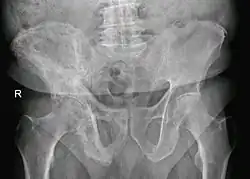

The exact cause is unknown, although leading theories indicate both genetic and acquired factors (see Causes). Paget's disease may affect any one or several bones of the body (most commonly pelvis, tibia, femur, lumbar vertebrae, and skull), but never the entire skeleton,[1][2][3] and does not spread from bone to bone.[4] Rarely, a bone affected by Paget's disease can transform into a malignant bone cancer.

- Pagetic bone has a characteristic appearance on X-rays. A skeletal survey is therefore indicated.